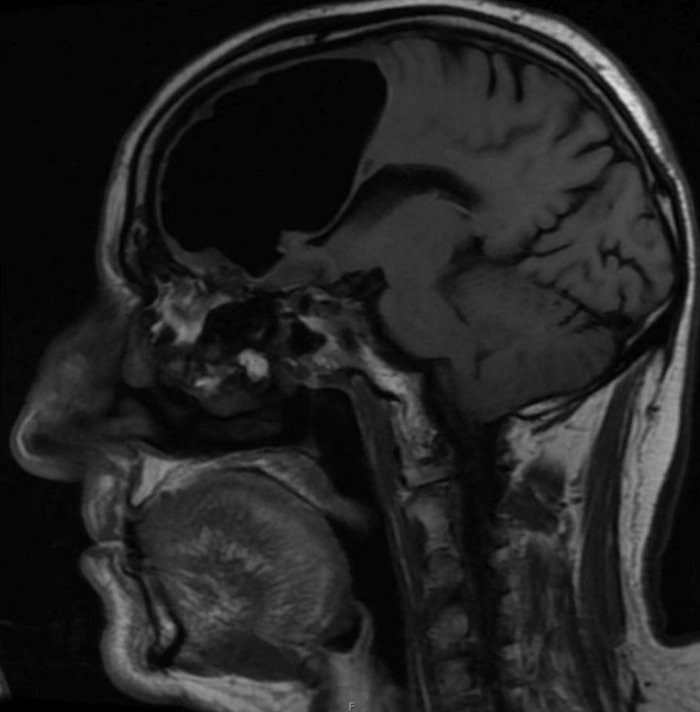

Ирландските медици съобщиха за един от най необичайните случай в своята

...... помощ и наблюдението над мъжа в течение на 12 седмици показали, че откритите „дефекти“ в главата му не представляват никаква опасност за живота му.

...... над мъжа в течение на 12 седмици показали, че откритите „дефекти“ в главата му не представляват никаква опасност за живота му. Превод и редакция: БЛИЦ